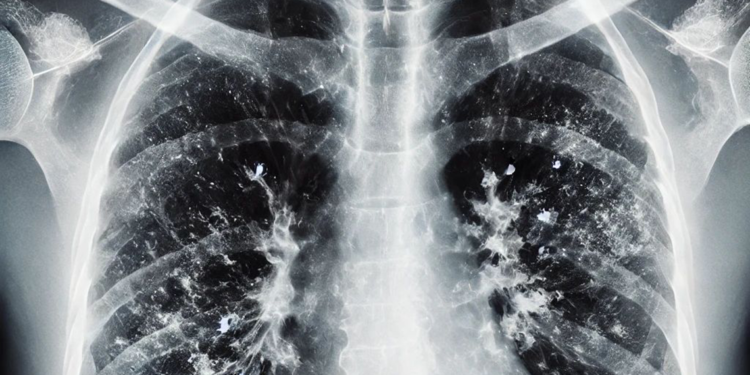

Mevsimsel grip, nezle ve diğer solunum yolu enfeksiyonları genellikle hafif seyretse de bazı durumlarda zatürreye dönüşerek ciddi komplikasyonlara yol açabiliyor. Uzmanlar, zatürrenin grip ya da soğuk algınlığıyla karıştırılabileceğini fakat bazı kritik belirtilerin ayırt edici olduğunu söylüyor. Yüksek ateş, titreme, aşırı halsizlik, balgamlı ve koyu renkli öksürük, nefes darlığı ve göğüs ağrısı gibi şikayetlerin zatürre ihtimalini güçlendirdiğini belirten uzmanlar, zatürrenin özellikle yaşlılar, bebekler ve kronik hastalığı olan bireylerde ağır seyredebileceğini belirtiyor.

Zatürrenin grip ya da soğuk algınlığıyla karıştırılabileceğini belirten Prof. Dr. Özlü, “Bu tür enfeksiyonlar genelde üst solunum yollarında yerleşir. Oradan başlar ve nezle, soğuk algınlığı, farenjit, sinüzit gibi üst solunum yolu enfeksiyonlarına yol açar. Bazen de alt solunum yollarına ilerleyerek bronşit, bronşiolit gibi hafif hastalıklara yol açabilir. Fakat zatürre, bu hastalıklar arasında en ağır olanıdır. Maalesef, şu sıralar pek çok hasta zatürreyi fark edemiyor ve teşhiste geç kalıyor. Oysa zatürrede erken tanı çok önemli. Hekimin, 4 saat içinde doğru tedaviye başlaması, zatürreye bağlı ölümleri anlamlı şekilde azaltıyor” ifadelerini kullandı.

Zatürre tanısında en önemli belirtilerin nefes darlığı ve öksürük olduğunu ifade eden Özlü, “Şikayetleriniz tedaviyle ya da tedavisiz olarak ilk birkaç gün içinde azaldıktan sonra tekrar ikinci bir atak yaşanıyorsa; ateşlenme ve şikayetlerde artış oluyorsa bu da zatürrenin eklendiğini gösterebilir. Nefes darlığı çok önemli bir belirti. Özellikle nefes alıp vermekte zorlanıyorsanız, özellikle bebeklerde ve yaşlılarda solunum sayısının dakikada 24’ün üzerine çıkması, nefes alıp verirken hırıltı olması, bebeklerde burun kanatlarının solunuma eşlik etmesi, nabız sayısının dakikada 120’nin üzerine çıkması gibi durumlar zatürre olasılığını güçlendirir. Öksürük de önemli bir belirti. Zatürrede öksürük genellikle yaş öksürüktür. Yani balgamlıdır. Balgamın koyu renkli olması; kahverengi, koyu sarı, koyu yeşil gibi ve kıvamlı olması zatürre ihtimalini artırır. Ateşin çok yüksek olmasıyla birlikte yan ağrısı dediğimiz, öksürürken ya da nefes alırken batıcı şekilde hissedilen bir yan ağrısı varsa, bu da zatürreye işaret edebilir” dedi.